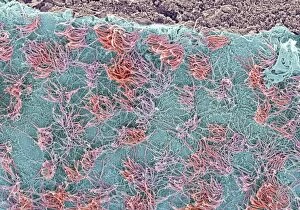

The central nervous system, the intricate network that governs our every thought and movement, is a marvel of complexity. From the delicate cerebellum tissue to the detailed light micrograph capturing its essence, we are reminded of its importance in maintaining balance and coordination. Anatomy comes alive as we explore the human brain from an inferior view. The intricacy of brain fibers is revealed through DTI MRI scans like C017/7099 and C017/7035, showcasing their vital role in transmitting information throughout this extraordinary organ. Artistic renderings bring us closer to understanding the medulla oblongata's significance within the brain. Its portrayal in various artworks allows us to appreciate how it controls essential functions such as breathing and heart rate. As we delve deeper into studying the central nervous system, models of the human brain provide invaluable insights into its structure and organization. Lateral views reveal countless regions responsible for cognition, emotion regulation, sensory perception, and motor control. Microscope slides offer glimpses into nerve cells' intricate architecture—a testament to their ability to transmit electrical signals at lightning speed. Meanwhile, glial stem cell cultures captured under a light microscope remind us of their crucial role in supporting neuronal function. Finally, artistic representations unveil the limbic system's enigmatic nature—an interconnected web responsible for emotions and memory formation. These captivating artworks allow us to visualize this complex network within our brains. Exploring these hints provides a glimpse into the awe-inspiring world of our central nervous system—the very foundation upon which our thoughts, actions, memories reside—reminding us just how remarkable our brains truly are.